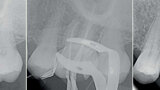

Fig. 6 : Différentes limes du système GeniusR

1. Orifice Opener court de 18 mm, n° 30 et conicite 8 % pour l’évasement du tiers cervical et la relocalisation des entrées canalaires.

2. Une lime n° 25.04 pour la préparation initiale jusqu’à’a la longueur de travail obtenue après exploration a l’aide de limes K manuelles jusqu’au numéro 15. Pour être utiliser de préférence en réciprocité, 90/30°,350 rpms.

3. Limes 30, 35, 40 ou 50 toujours en conicité .04 à choisir selon le profil anatomique initial du canal.